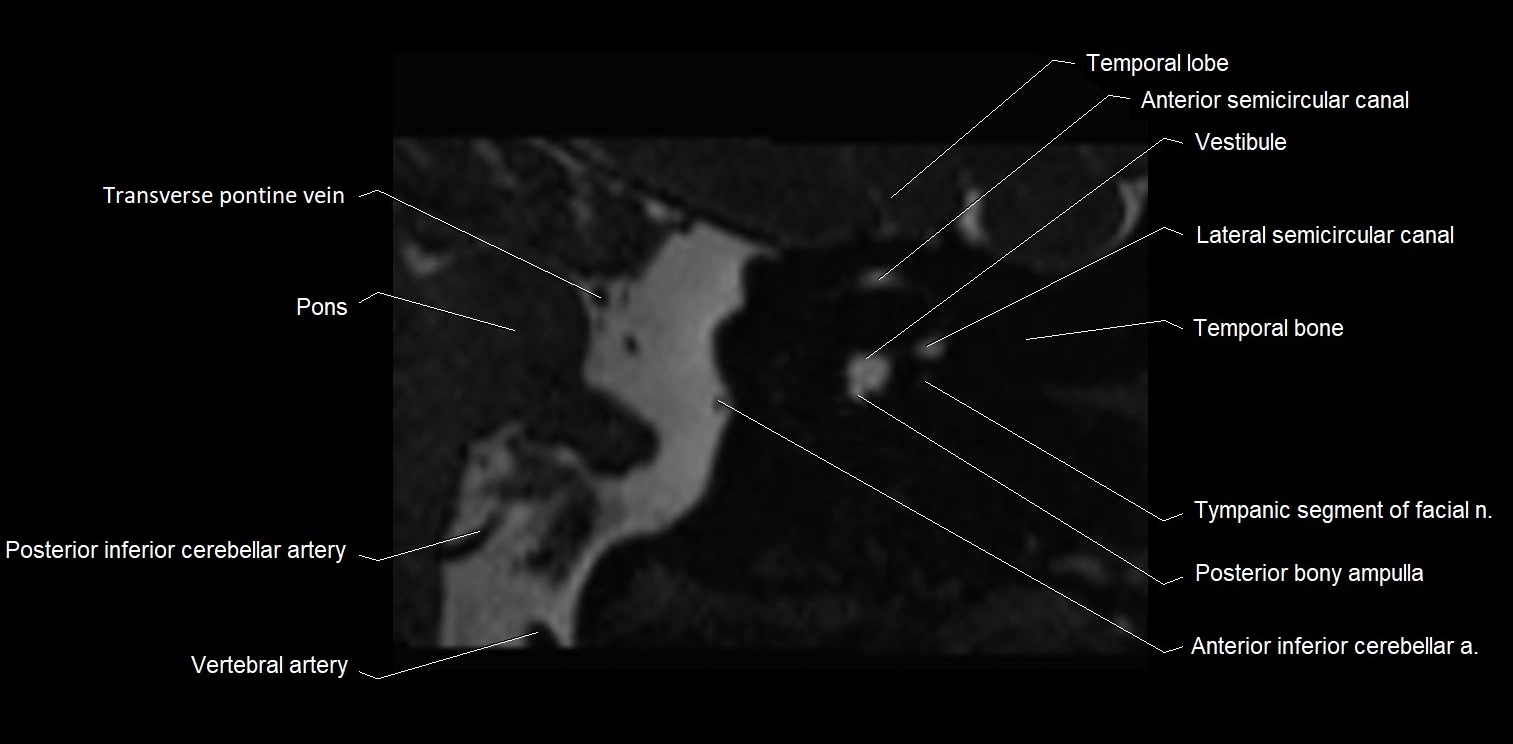

MRI images

image